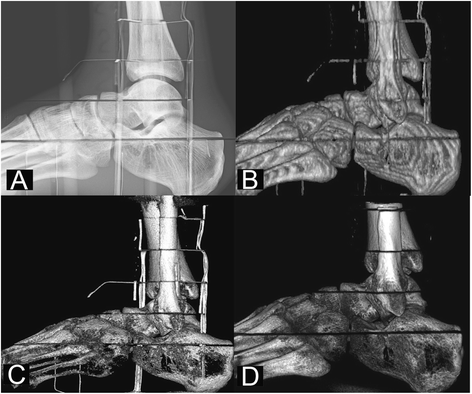

The effective doses and dose contribution of each organ are shown in Table 4. The sagittal projections (cropped images) of the exposed volume using conventional radiography, two CBCT and MSCT devices excluding toes are presented in Figure 4.

Figure 4

Sagittal ankle projections using the Shimadzu FH21-HR radiography device (A), the Siemens Sensation Open MSCT device (B), the NewTom 5G CBCT device (18 × 16 cm FOV) (C) and the Planmed Verity CBCT device (D).